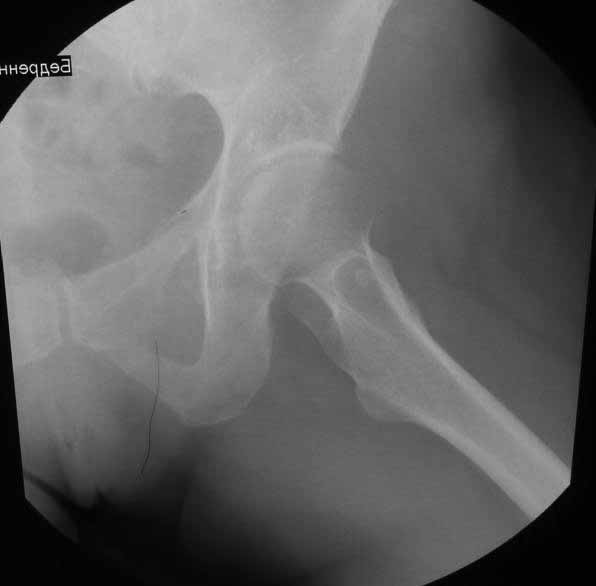

Пациентка 45 лет. Бесцементное эндопротезирование левого тазобедренного сустава 6 лет назад (впадина RM, Mathys, металл-металл, ножка Зульцеровская). За 10 лет до протезирования – коррегирующая остеотомия бедренной кости, которая не срослась в течение года до удаления пластины, а затем срослась в течение 3 месяцев иммобилизации в кокситной повязке. После протезирования получилось наблюдать пациентку почти постоянно, поскольку через 2 года синтезировал ей лодыжки на оперированной стороне, затем, через несколько месяцев удалил фиксаторы, а в 2009г. резецировал мениск на противоположной стороне. Боли все эти годы не беспокоили. Пациентка чуть выше среднего роста, вес тела нормальный. Физические нагрузки переносила хорошо. Работает на 7 этаже без лифта. Год назад экстирпация матки по поводу лейомиомы больших размеров. Несколько месяцев назад появились боли в области левого тазобедренного сустава. При рентгеновском и КТ исследованиях (июль с.г.) – нестабильность тазового компонента. От предложенной замены протеза пациентка на тот момент, слава богу, отказалась. Через какое то время боли в области левого тазобедренного сустава практически полностью прошли, а около 2 месяцев назад появилось ощущение патологической подвижности таза и боли в паху справа, которые через некоторое время уменьшились, а потом снова усилились после значительных физических нагрузок (много ходила по песку на пляже, носила тяжести). Ежедневно принимала диклофенак. На рентгенограммах – переломы правой лонной кости. Сейчас госпитализирована из-за болей в паху справа. Боли слева не беспокоят. На фоне снижения нагрузок в стационаре боли значимо уменьшились. Способна ходить без средств дополнительной опоры.

-правильно ли я расцениваю переломы как стрессовые на фоне неполноценного таза (pelvic insufficiency stress fractures)?

На представленных снимках тазобедренный сустав до и сразу после операции, затем 2 снимка 2009г., когда ничего не беспокоило, затем КТ 2-х месячной давности и вчерашние рентгенограммы обоих тазобедренных суставов.